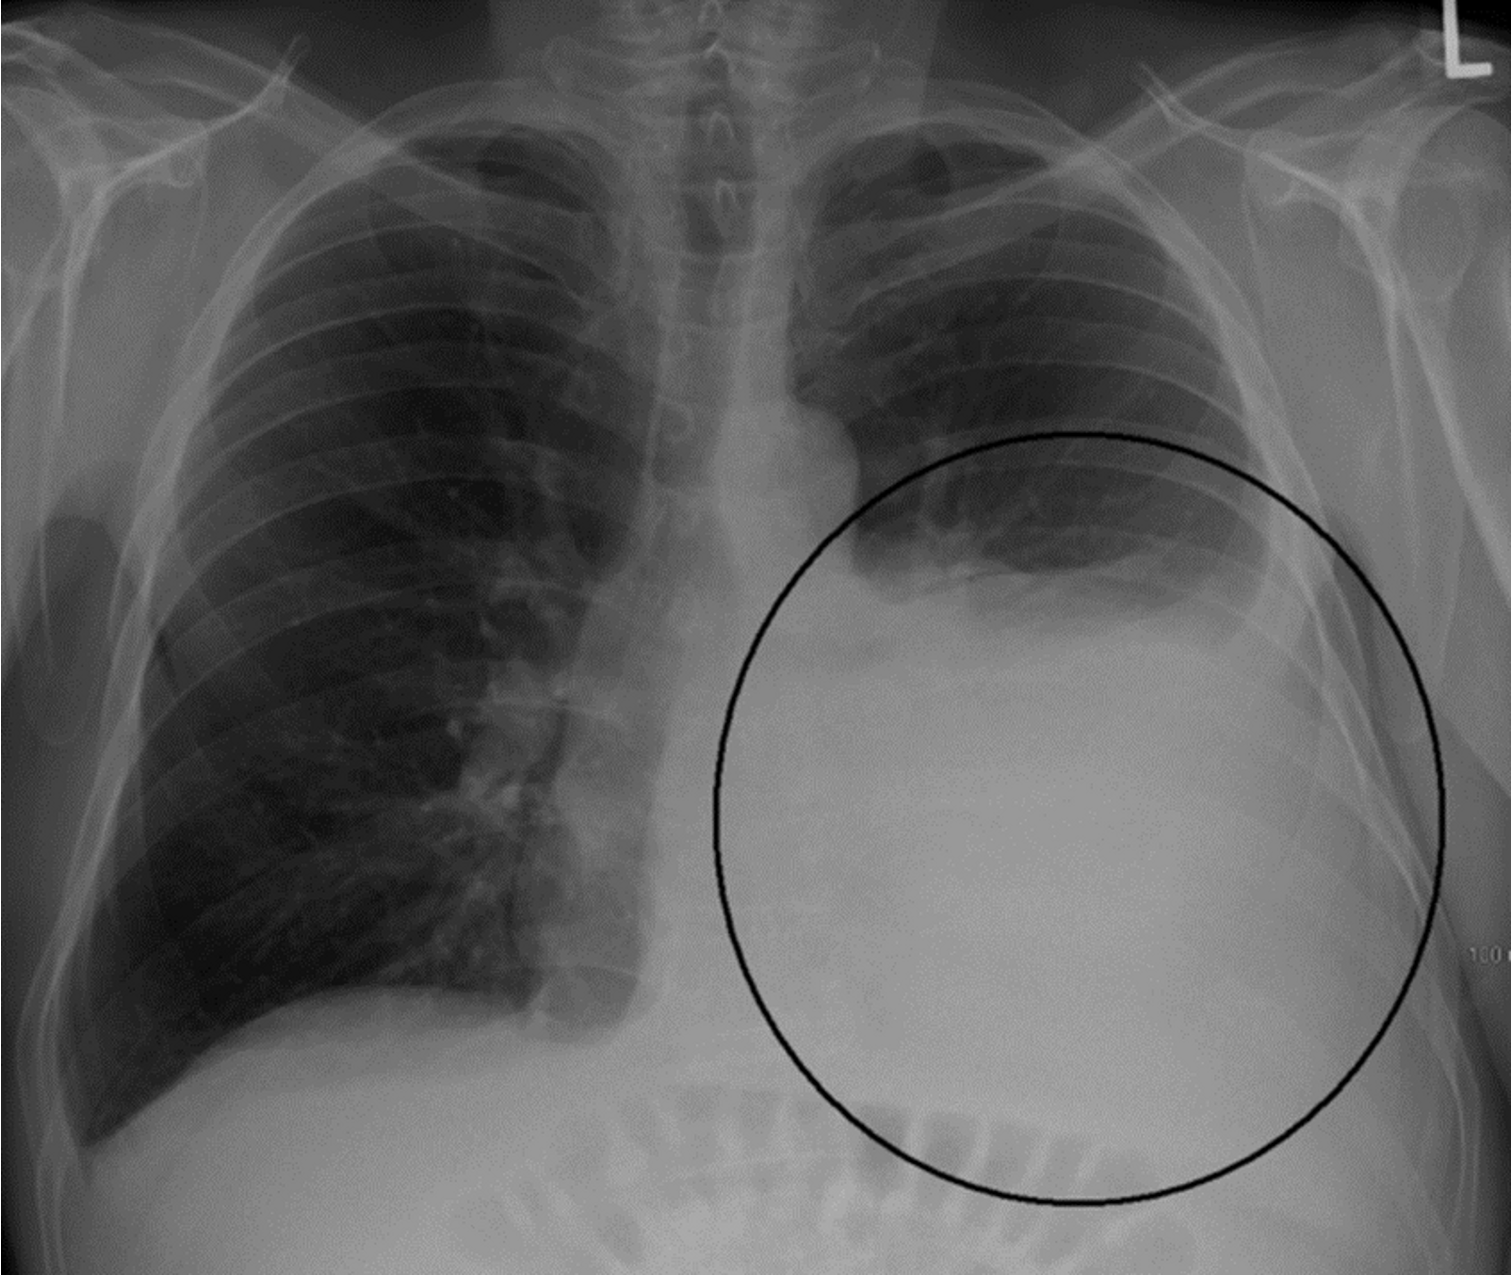

Pleural effusion with tracheal deviation